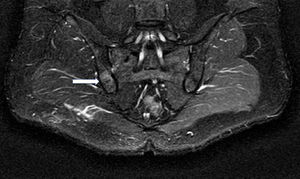

El paciente refería dolor en nalga derecha, que le despertaba por la noche, mejorando con antiinflamatorios no esteroideos (AINE). No había presentado ningún antecedente traumático, fiebre, artritis ni en la anamnesis aparecían datos relacionados con espondiloartritis o infecciones recientes. La exploración física era completamente normal, siendo las maniobras de sacroilíacas negativas (Fabere, apertura, cierre y Laguerre), y no presentando limitación funcional articular periférica ni axial. La exploración neurológica no reveló ningún dato patológico. La analítica realizada no presentaba alteraciones, con normalidad en los reactantes de fase aguda. En cuanto a las técnicas de imagen, en la radiografía simple de pelvis no se objetivaron alteraciones óseas evidentes, por lo que se solicitó resonancia magnética nuclear (RMN) de sacroilíacas, apreciándose área hipointensa en secuencia T1 (fig. 1) e hiperintensa en STIR (fig. 2) en borde ilíaco de sacroilíaca derecha, con zona central isointensa en T1 (fig. 1) e hipointensa en STIR (fig. 2), orientando hacia el diagnóstico definitivo de osteoma osteoide, que se confirmó mediante tomografía computarizada (TC). El paciente se trató mediante ablación por radiofrecuencia guiada por TC quedando asintomático.